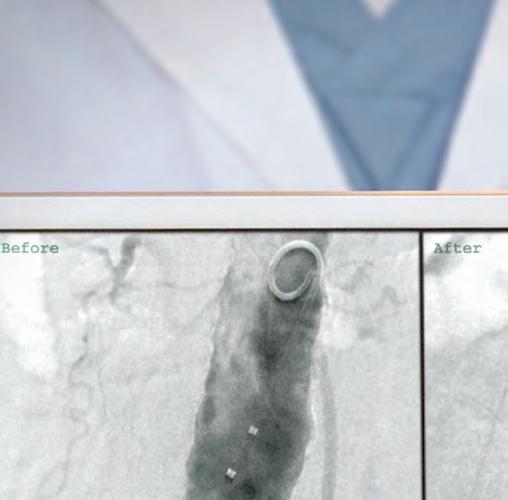

CHICAGO – Drug-coated balloons show promise of being a long-sought major advance in the endovascular treatment of stenotic arteriovenous fistulae and grafts for hemodialysis access, Syed M. Hussain, MD, said at a symposium on vascular surgery sponsored by Northwestern University.

Something significantly better than today’s standard treatment options is needed, according to Dr. Hussain. Medicare pays out more than $50 billion annually for the treatment of patients with end-stage renal disease, and a hefty chunk of that money goes for oft-repeated procedures aimed at preserving the patency of the access sites.

“Primary patency rates leave much room for improvement,” observed Dr. Hussain, a vascular surgeon at the Christie Clinic in Champaign, Ill.

Indeed, the 50% primary patency rate at 6 months that was optimistically declared a “reasonable goal” in the 2006 Kidney Disease Outcomes Quality Initiative is actually farfetched using the conventional tools.

“That 50% patency at 6 months would be a tall order to try to meet. Anybody in this room that does fistulography and angioplasty knows the numbers are actually a lot lower than 50%,” said Dr. Hussain.

Plain old balloon angioplasty, the standard first-line intervention for stenotic hemodialysis access sites, has a 6-month patency rate of about 30%. Bare-metal stents push the rate up to about 39%. Covered stent grafts are the most effective of the conventional treatment modalities, with a 6-month patency of 51%-53%; however, they are widely considered too expensive for routine use.

Drug-coated balloons (DCBs) have been available for close to 3 years for treatment of lower-extremity peripheral artery disease, where they have achieved considerable success. The Food and Drug Administration has approved three commercially available DCBs for this purpose: Bard’s Lutonix 035 AV, Medtronic’s IN.PACT Admiral, and most recently the Stellarex DCB.

In addition, the Lutonix DCB is approved for treatment of dysfunctional or stenotic arteriovenous (AV) fistulae on the strength of the positive results of the first prospective randomized multicenter trial of a DCB versus balloon angioplasty for AV access stenosis as reported at a conference in Leipzig, Germany, in 2017 and summarized by Dr. Hussain.

The breakthrough for DCBs as a potential game changer in dialysis access stenosis came with the discovery that venous smooth muscle cells are much more sensitive to paclitaxel and other antiproliferative drugs than are arterial smooth muscle cells. All three commercially available DCBs utilize paclitaxel as their active agent. Multiple small single-center studies involving off-label use of the DCBs for dialysis access stenosis strongly suggested 6-month patency rates were higher than with balloon angioplasty. Then came the core lab-adjudicated Lutonix multicenter trial, in which 285 hemodialysis patients at 23 sites were randomized to the DCB or balloon angioplasty. Participants had to have a target lesion less than 10 cm long and had to undergo successful predilatation with high-pressure balloon angioplasty.

That being said, the 8-month target lesion primary patency rate was 61.6% in the Lutonix DCB group, compared with 49.4% for percutaneous angioplasty, a statistically significant and clinically meaningful difference. Moreover, 66 interventions were required to maintain target lesion patency during that time frame in the DCB group, versus 94 in the angioplasty group; that translated to a 30% reduction in repeat interventions.